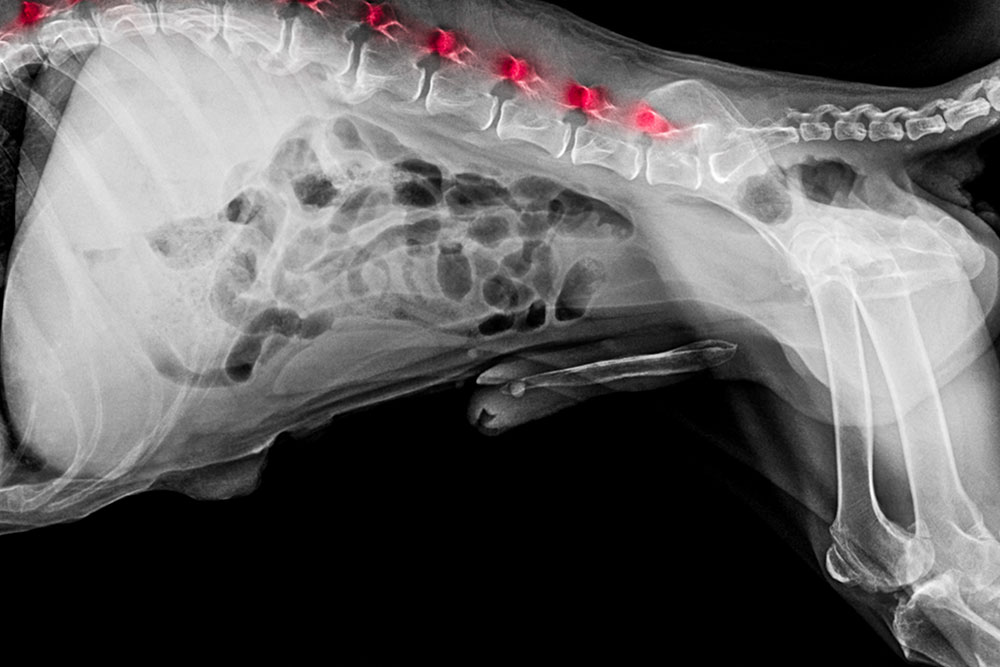

IVDD, or intervertebral disc disease, occurs when one or more of the cushioning discs between the vertebrae of the spine degenerates, bulges, or ruptures. When disc material presses against the spinal cord or the nerve roots branching off it, the result is pain, neurological dysfunction, or both. The severity depends on how much material has herniated and how much compression exists.

There are two main types. Type I involves sudden, forceful disc herniation, common in chondrodystrophic breeds, dogs bred with shortened limbs and long bodies, where disc tissue calcifies early. Type II involves a slower, gradual bulging of disc tissue, more often seen in larger breeds and older dogs.

IVDD is classified in five stages that reflect how severely the spinal cord is being affected:

- Stage 1: Pain only, no coordination problems. The dog walks normally but may be stiff or hold their head low.

- Stage 2: Still walking, but with proprioceptive deficits (paw knuckling, wobbling). Moderate to severe pain.

- Stage 3: Able to move the legs but cannot stand or walk independently. One or more paws may drag.

- Stage 4: Paralyzed and unable to walk, but deep pain sensation is still present. Bladder and bowel control may be lost.

- Stage 5: Paralyzed with no deep pain sensation in the feet. This is the most severe stage, and timing is critical.